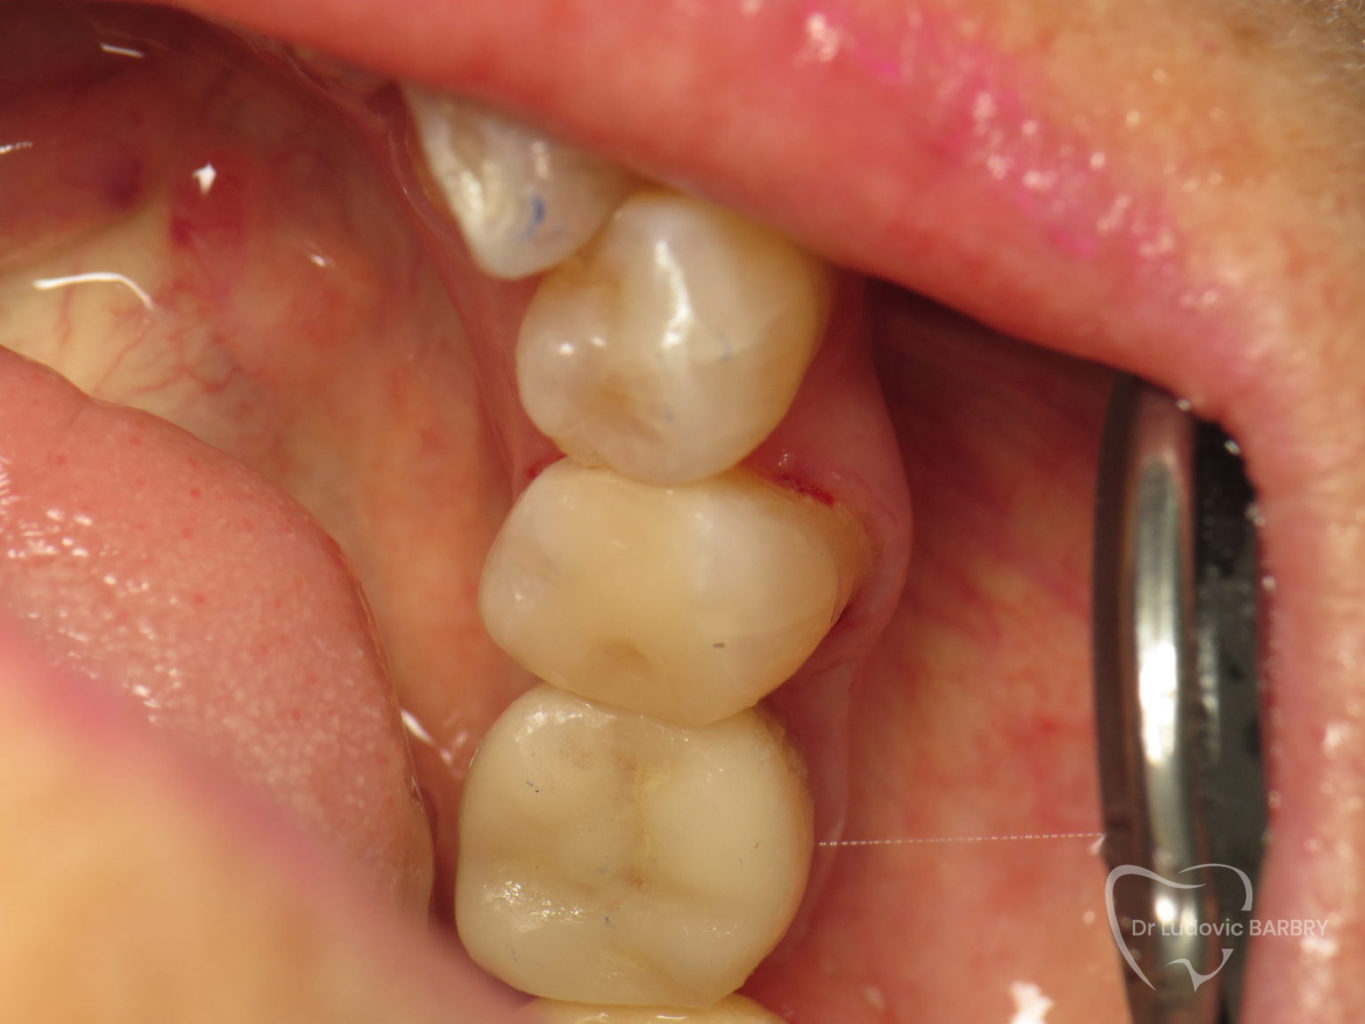

Inlay / Onlay céramique

Les inlays et les onlays sont des alternatives aux plombages ou aux résines de volume important. Il s’agit d’une technique moderne d’obturation qui permet d’éviter une prothèse beaucoup plus mutilante pour la dent et préserve l’intégrité de la dent en évitant les récidives de caries.

Cette pièce en céramique est fabriquée sur mesure et posée dans la séance grâce aux techniques modernes de CFAO (conception et fabrication assisté par ordinateur) que nous disposons au sein du cabinet.